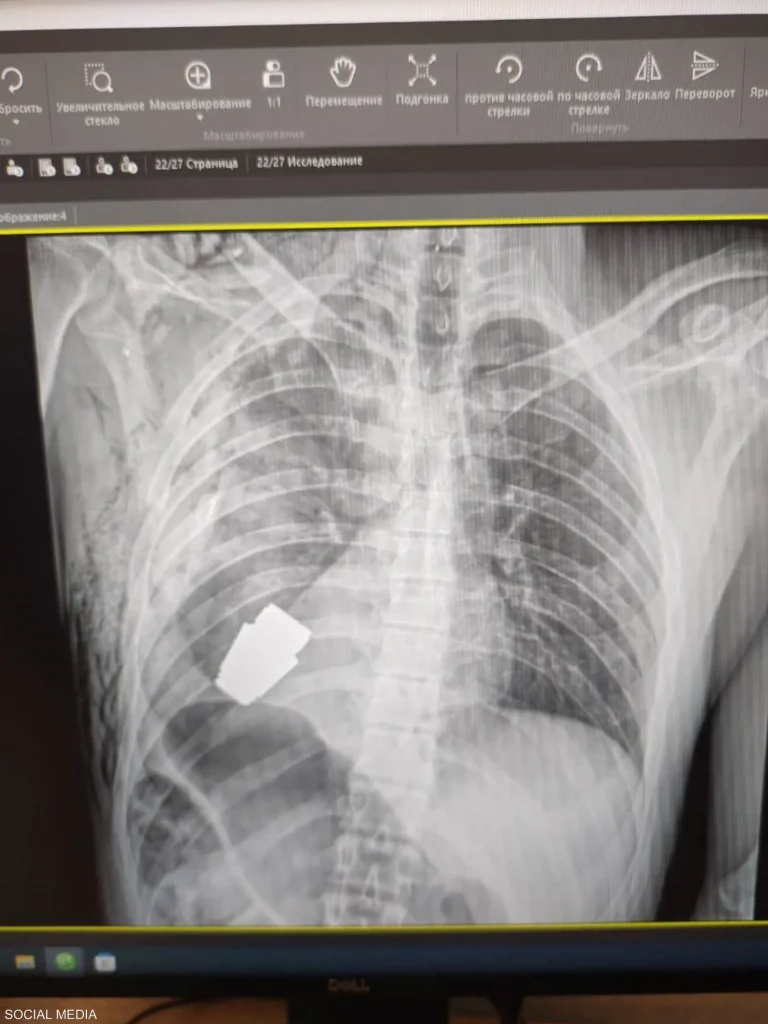

حالف الحظ والجهود الطبية أحد الجنود الأوكرانيين وبقي على قيد الحياة بعد أن استقرت قنبلة حية في جذعه خلال معركة في باخموت بأوكرانيا، وكان لا بد من التدخل لإزالتها جراحيا.

واضطر الجراح الأوكراني اللواء أندري فيربا إلى إجراء الجراحة علما أن القنبلة اليدوية يمكن أن تنفجر في أي لحظة.

وأكد حاكم المنطقة، سيرهي بورزوف، في منشور على “فيسبوك” ليلة الاثنين أن “أطبائنا العسكريين أجروا عملية لإزالة قنبلة غير منفجرة من جسد جندي”.

ومع ذلك، قال بورزوف إن الدكتور فيربا كان قادرا على إجراء الجراحة بنجاح وإزالة القنبلة اليدوية.

وأضاف بورزوف أن “التدخل العملياتي كان ناجحا وتم إرسال الجندي المصاب لإعادة التأهيل والتعافي”.

وأفادت صحيفة ديلي ميل أن الدكتور فيربا، أحد الجراحين الأكثر خبرة في أوكرانيا، يعمل في منطقة دونباس منذ عام 2014، حصل على جوائز الدولة للدكتوراه الفخرية في أوكرانيا ودكتوراه في العلوم الطبية وقاد الآلاف من العمليات الميدانية.